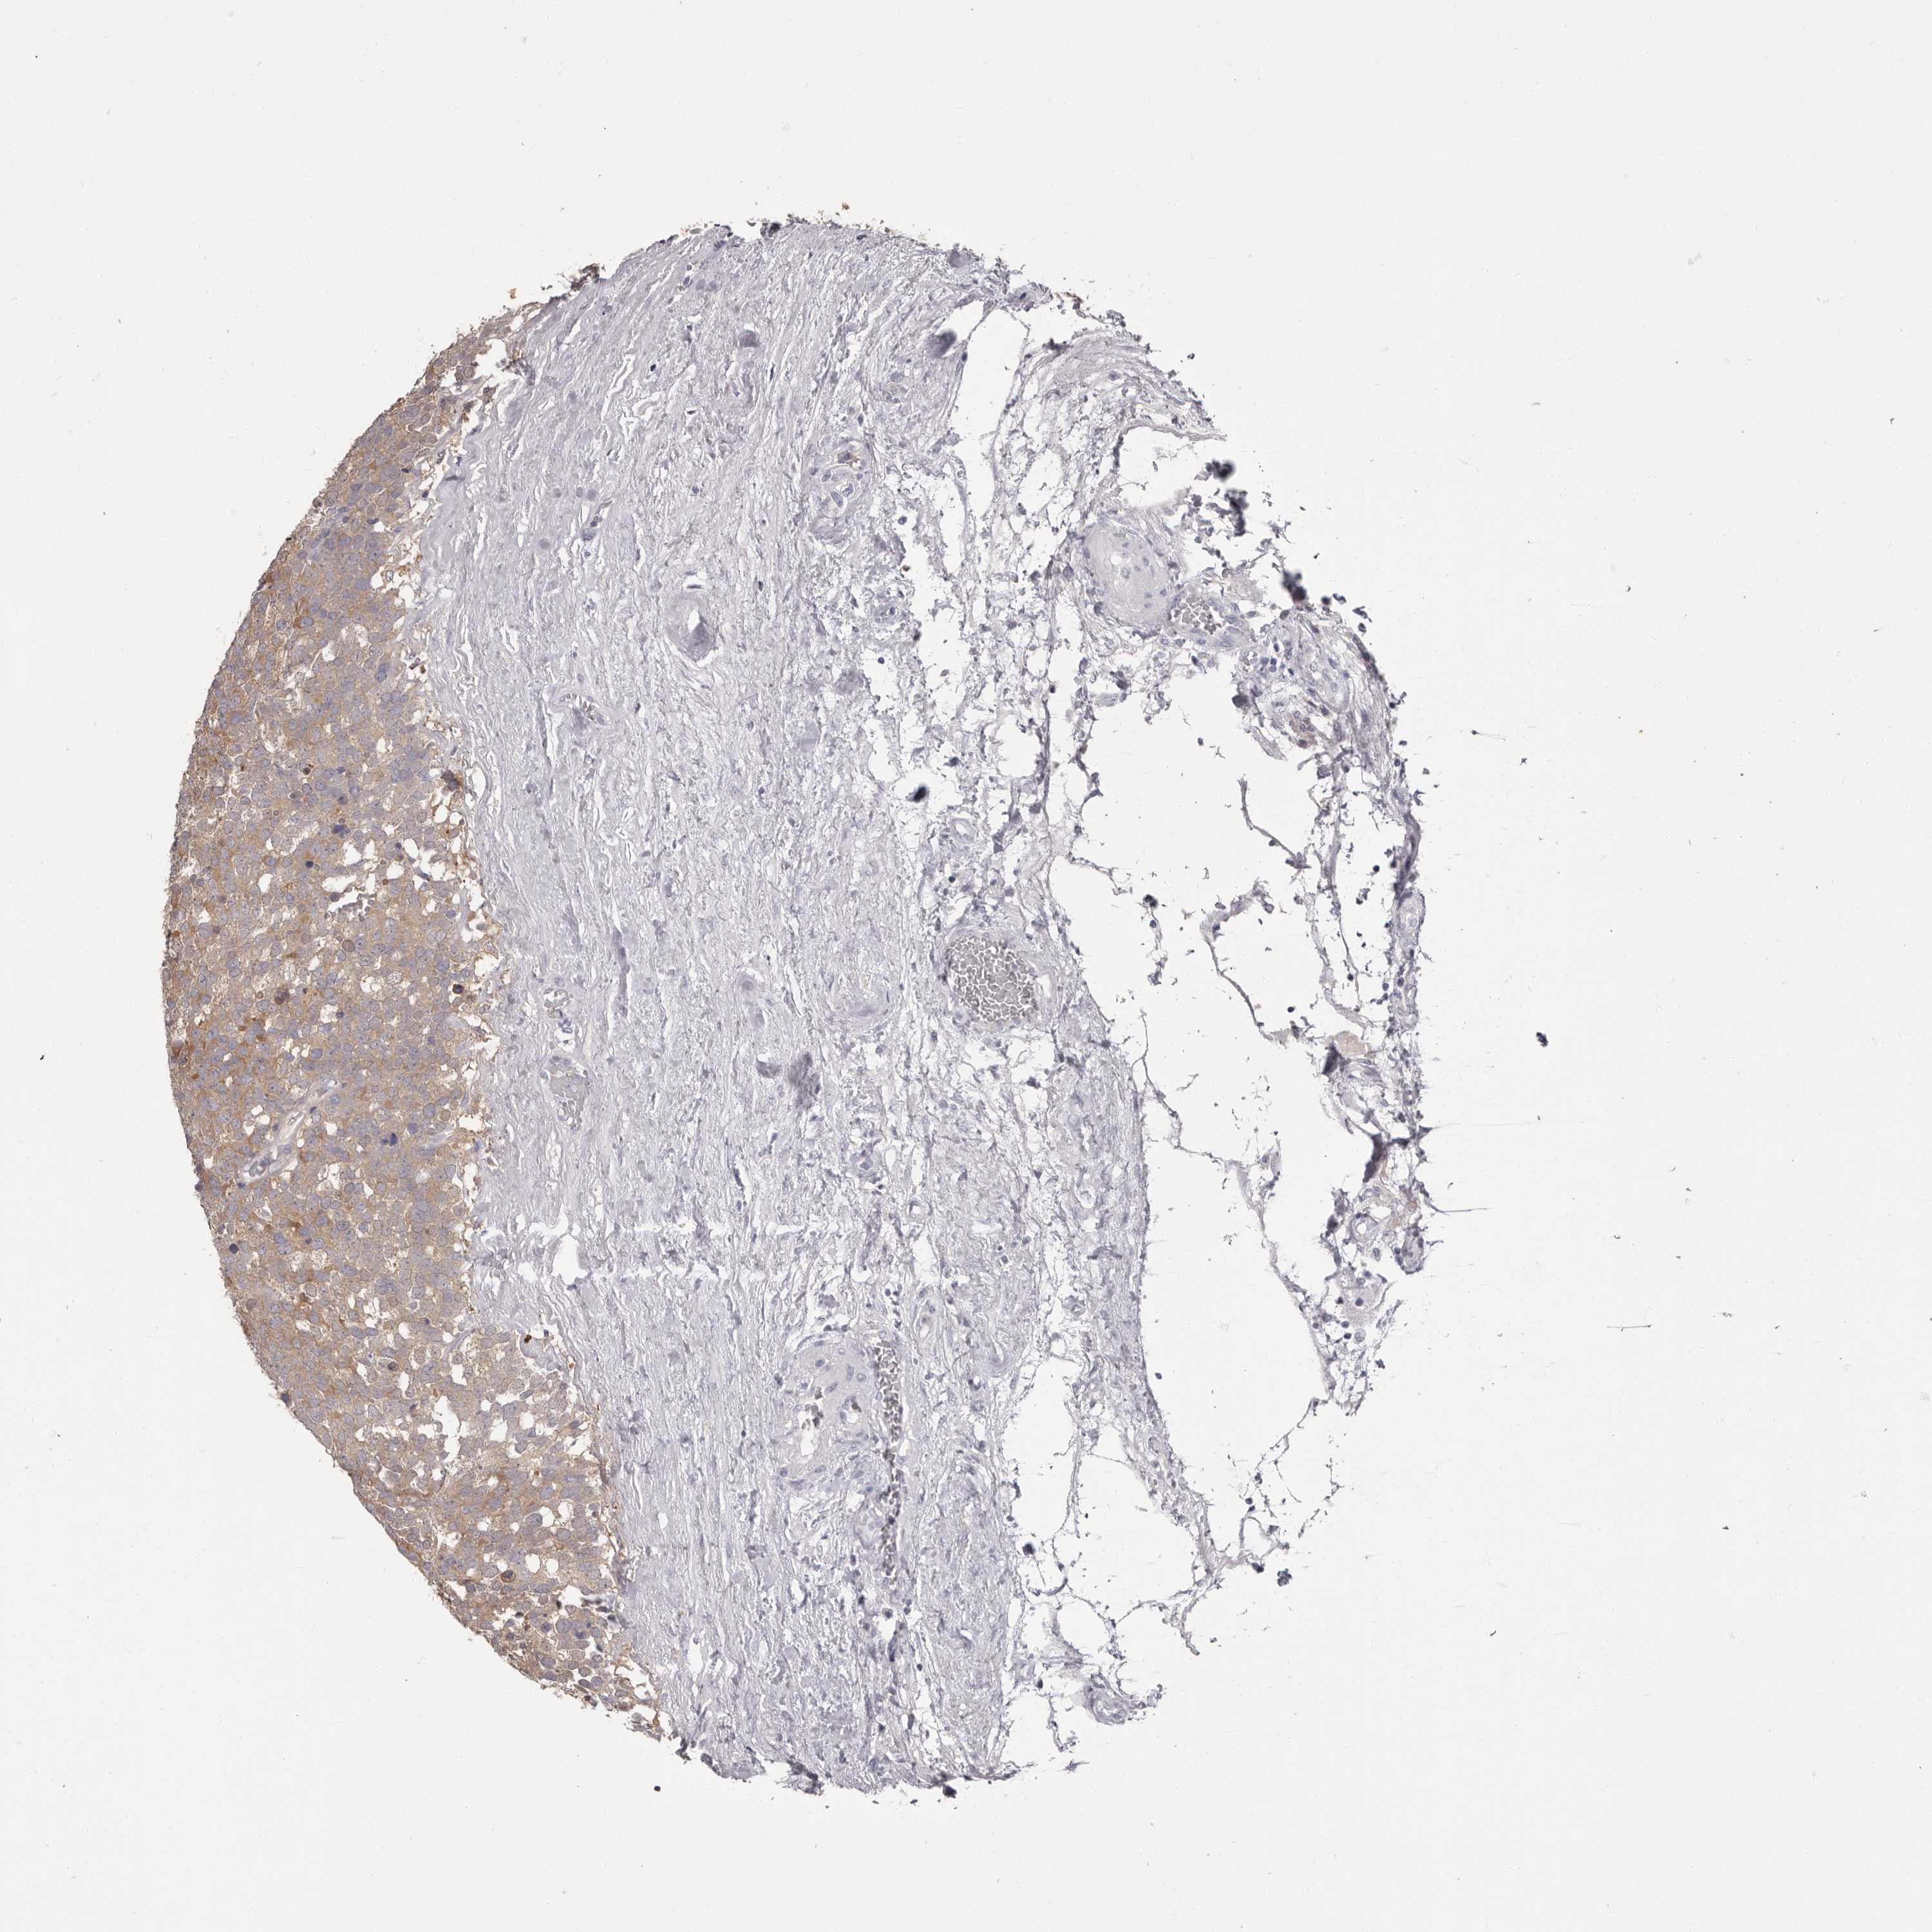

TESTIS CANCER - Protein expressioni

A mouse-over function shows sample information and annotation data. Click on an image to view it in a full screen mode. Samples can be filtered based on level of antibody staining by selecting one or several of the following categories: high, medium, low and not detected. The assay and annotation is described here.

Note that samples used for immunohistochemistry by the Human Protein Atlas do not correspond to samples in the TCGA dataset.

Antibody stainingi

Antibody staining in the annotated cell types in the current human tissue is reported as not detected, low, medium, or high, based on conventional immunohistochemistry profiling in selected tissues. This score is based on the combination of the staining intensity and fraction of stained cells.

Each image is clickable and will lead to virtual microscopy that enables deeper exploration of all samples and also displays staining intensity scores, fraction scores and subcellular localization as well as patient and tissue information for each sample.

Antibody HPA029700

Antibody HPA029701

Antibody HPA029702

Antibody HPA029703

Carcinoma, Embryonal, NOS

Seminoma, NOS